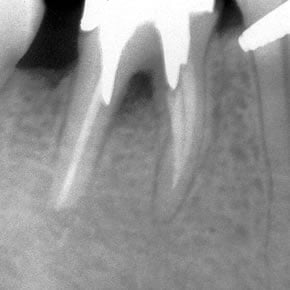

Template for x-rays

Biolight® DRILL-FREE posts are available in bundles of 4, 6, 9 and 12 strands. The post size is selected based on the width of the canal at the coronal area. Depending upon the canal width at the apical stop, a certain number of strands must be pushed to the stop. Both of the measurements are made with the assistance of a radiograph and the template that is included in the TRAINING KIT.